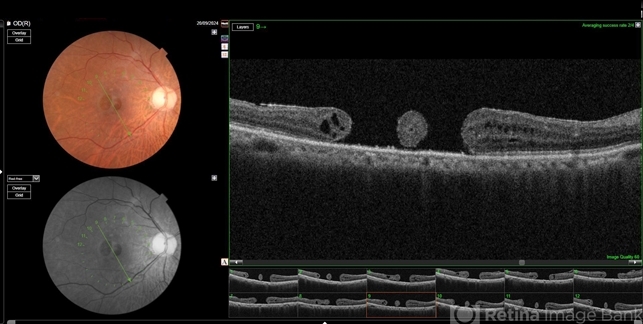

- Double hole

- traumatic macular hole, double

Optical coherence tomography system

Topcon Maestro 2 - Description

- OCT image of a 62 year old man after a blunt trauma by a tennis ball with a vision of CF 3 mt in the right eye.